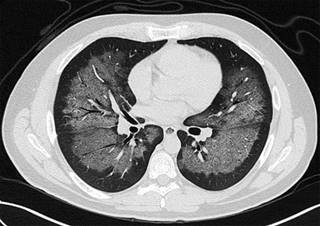

Hombre de 39 años, originario y residente de la Ciudad de México, licenciado en Administración. Con antecedente de neumopatía crónica por uso y abuso del tabaco, con un índice tabáquico de 20.7, además de dislipidemia de reciente diagnóstico en tratamiento con fenofibrato 250 mg vía oral cada 12 horas. Inicia su padecimiento el día 21 de junio del año en curso, posterior a exposición con líquido limpiador de calzado a base de heptano, isobutano, petróleo de fracción alifática ligera y propano; con un tiempo de contacto de dos horas, mientras se encontraba en un sitio con mala ventilación. Dos horas posteriores a la exposición inició con tos seca intermitente, progresando a disnea de pequeños esfuerzos, dolor torácico opresivo que se exacerbaba a la inspiración, motivo por el cual acudió a valoración a una unidad médica en donde se le inició abordaje diagnóstico con toma de radiografía de tórax, laboratorios y gasometría, encontrándose con datos sugestivos de neumonitis química; se inició manejo con esteroides intravenosos y broncodilatadores a dosis no especificada, se egresó a domicilio a petición del paciente. Veinticuatro horas posteriores a su egreso persistía con la misma sintomatología, por lo que acude al Servicio de Urgencias del Hospital Ángeles del Pedregal. A su ingreso se encontraba taquicárdico y con taquipnea con tensión arterial de 130/80 mmHg, afebril, saturación de oxígeno de 88% al aire ambiente. Inicialmente se tomó gasometría arterial con datos de alcalosis respiratoria crónica, mejorando la saturación con aplicación de oxígeno suplementario por puntas nasales llegando hasta 94% de saturación. A la exploración física faringe con hiperémica, tórax simétrico, con adecuados movimientos respiratorios, a la auscultación con ruidos respiratorios disminuidos de predominio en hemitórax izquierdo, vibraciones vocales disminuidas en ambos hemitórax, sin estertores o sibilancias, así como taquicardia de 120 por minuto; resto de la exploración sin alteraciones. Se solicitó tomografía simple de tórax (Figura 1), evidenciándose patrón alveolar central y difuso en lóbulos superiores, lóbulo medio, segmento lingular, segmento superior y segmento medial de ambos lóbulos inferiores con lo que se hizo el diagnóstico de neumonitis. Con estas evidencias y de acuerdo con su condición clínica se decidió su ingreso a la Unidad de Terapia Intensiva, con diagnóstico de neumonitis y quemadura química de la vía aérea, clasificándose como SOFA 2 de puntos, con una mortalidad de 6 al 8%. Se tomó electrocardiograma el cual mostró ritmo sinusal y sin datos de dilatación de cavidades y/o presencia de arritmias; los laboratorios con leucocitosis a expensas de neutrófilos, proteína C reactiva 86.57 mg/L, VSG 1 mm/hora, procalcitonina 11.87 ng/mL, glucosa 122 mg/dL, sin alteración a la función renal en niveles séricos. El tratamiento inicial fue a base de salbutamol/ipratropio 250 μg cada ocho horas, budesónida 800 μg cada seis horas, metilprednisolona un g cada 24 horas por tres días, meropenem un g cada ocho horas y claritromicina 500 mg cada 12 horas. Durante sus primeras 24 horas de estancia en la unidad, continuaba con persistencia de taquipnea (frecuencia respiratoria [FR] 35 respiraciones/min), decidiéndose manejo avanzado de la vía aérea, manteniéndose con ventilación mecánica asistida por 96 horas, en modo controlado por volumen (FR 14, VC 600, sensibilidad 2.1, PEEP 10), con parámetros de distensibilidad estática de 125 y distensibilidad dinámica 44.5. Por mejoría de imagen radiográfica y menor dependencia a la VMA, se realizó extubación sin presentar complicaciones, manteniendo adecuada saturación con puntas de alto flujo. Se muestra la progresión radiográfica (Figura 2) en la cual se evidencia mejoría de la radiopacidad generalizada en el parénquima pulmonar.

Figura 1: Tomografía simple de tórax, con patrón alveolar central y difuso en lóbulos superiores, lóbulo medio, segmento lingular, segmento superior y segmento medial del lóbulo inferior de ambos pulmones sugestivo de neumonitis.